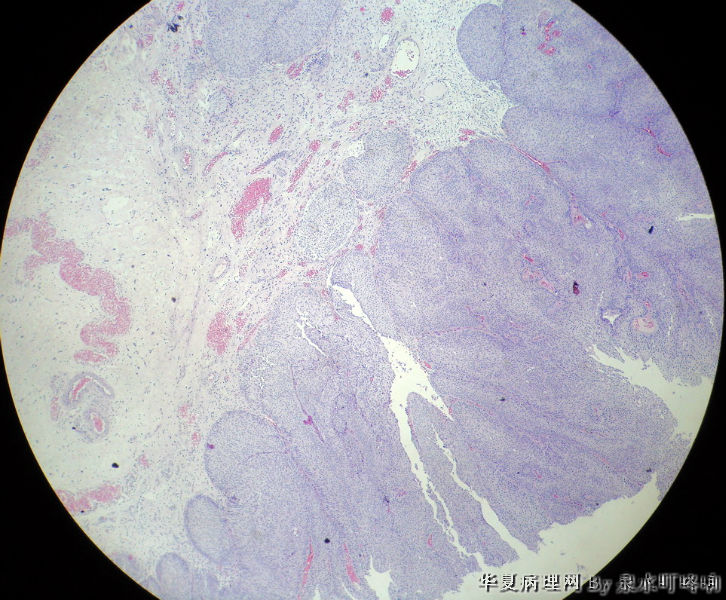

膀胱肿物

男,76岁,血尿一个月,发现膀胱肿物,行切除术,肿物位于右侧膀胱后外侧壁,约1.5×1.5×1.5厘米。

大体:灰白肿物一个,大小约2×1.1×0.9厘米,切面灰白,质中。

尿路上皮癌,低级别。

低级别非浸润性乳头状尿路上皮癌

(膀胱)非浸润性乳头状尿路上皮癌,低级别

低级别尿路上皮癌。至于浸润的问题还请楼主仔细观察切片,总感觉那种推进式的生长模式有浸润的嫌疑,临床上浸润与否治疗方式是不一样的。

Dx: High grade papillary urothelial carcinoma because: 1. nuclear chromasia (fig 13) and coarse chromatin. 2, almost all nuclei have prominent  nucleoli. 3, Nuclear pleomorphism (some nuclei are three times larger than smaller ones). 4. Nuclear membrane irregularity. 5. mitosis can be seen far away from the basement membrane. 6. a good portion of the neoplastic cells loss orientation that should be perpendicular to the basement membrane. 7. Low power view shows papillary branching and fusion. 8. patient's age

However, this should be the low end of the spectrum of high grade urothelial carcinoma. Careful search might reveal some focal microinvasion.or urothelial carcinoma in situ.